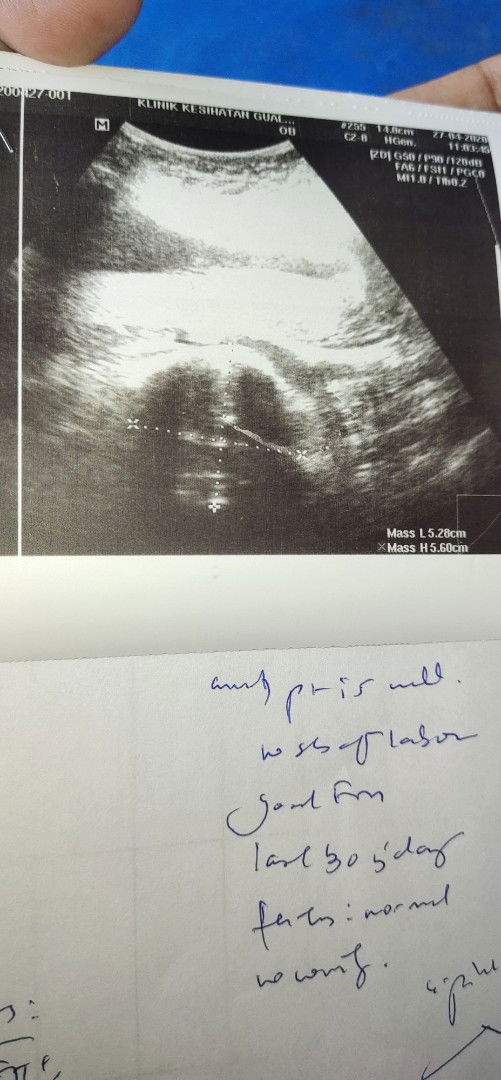

2 x scan nampak ketulan kat luar pada sarung baby.. Kat bawah. Doct refer ke pakar. Skarang usia kandungan 17 w 5 d.. Saya bimbag.. Ada kes macam saya..

2 x scan nampak macam ketulan ..kene refer pada pakar.. Ketulan kat luar sarung baby. Sekarang 17w 5 hari

Scan pertama nampak ketulan mcm kat pic tu.. Skarang usia kandunag 17 minggu + repeat scan skali lgi minggu dpn utk pastikan ketulan.. Kandungan ank ke 4..harap semuanya x membimbangkn. Ada ke ibu2 mcm kes saya